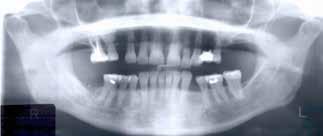

overbid (VOB). Papillen mellem 1+1 er betydeligt reduceret pga. fæstetab, og de mesialt kippede 1+1 har resulteret i en ”dark triangle”. Den facioorale funktion er for nuværende i.a. Panoramarøntgen (Fig. 1, I) viser marginalt knogletab i begge kæber og fravær af 8,7+7,8 og 8,7-8.

Objektivt anbefales behandling af det dybe bid, som ubehandlet forventes at forværres yderligere over tid. Patienten har ønske om behandling med æstetisk ortodontisk apparatur, alignere, og det vurderes muligt at behandle malokklusionen med alignere. Dog anbefales det generelt, at alignere undgås eller benyttes med væsentlige modifikationer af alignerens retention ved tandmobilitet, da dette ellers kan medføre jiggling, når aligneren tages af og på mange gange dagligt. På den anden side er der nogen evidens for, at alignerbehandling er associeret med bedre renhold og parodontal sundhed sammenlignet med fast apparatur (16).